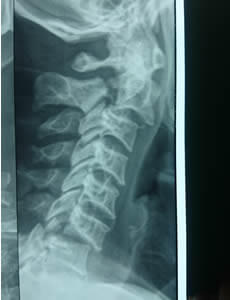

Dolor de Cuello